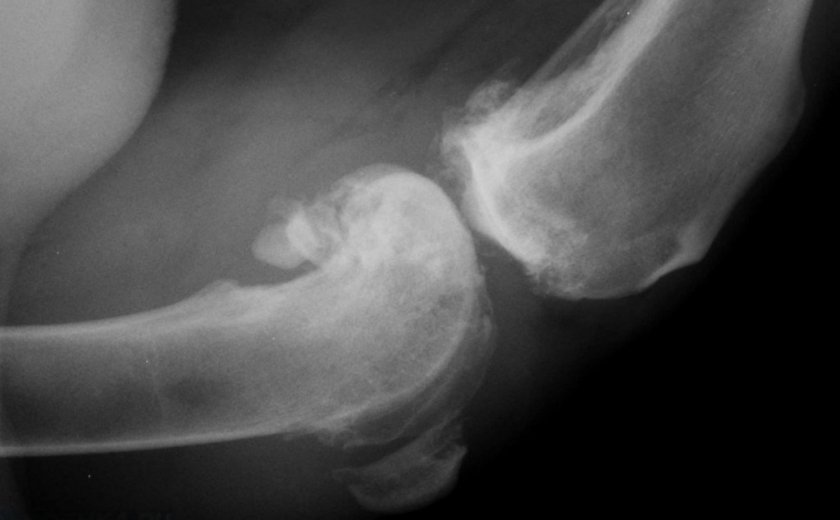

Для диагностики врач проведёт анализы крови и мочи. Это поможет выявить наличие или отсутствие бактериальной причины недуга. Затем назначит:

- рентген;

- компьютерную томографию;

- сбор жидкости суставов.

Это позволяет выявить любые признаки повреждения костной ткани. Так, на рентгене можно заметить все возрастные особенности и изменения тканей. А компьютерная томография позволяет получить 3D модель сустава.